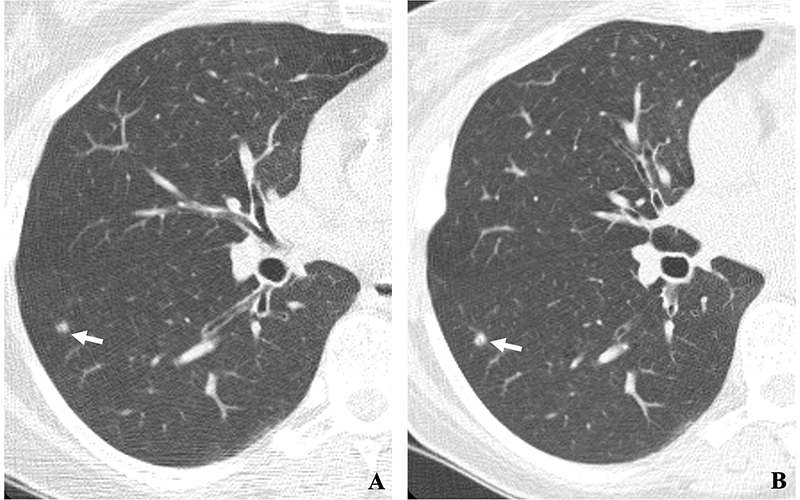

(A, B) Two annual repeat low-dose CT scans in a woman who was 60 years old at baseline enrollment in 1999. At baseline enrollment, she was currently smoking and had a 30-pack-year smoking history. No nodules were identified on baseline low-dose CT scans. On the sixth annual low-dose CT scan (B), a right lower lobe solid nodule (arrow) measuring 4.5 mm in maximum diameter was identified. The nodule could be identified in retrospect on the prior annual CT scan (arrow in A), when it measured 2.0 mm in maximum diameter. Estimated tumor volume doubling time was 161 days. Lobectomy was performed 2 months later, and diagnosis of stage 1aN0M0 moderately differentiated adenocarcinoma measuring 6.0 mm in maximum diameter was made. Expert pathologic panel review (22) of the pathologic specimen updated the diagnosis to adenocarcinoma with mixed subtype (80% acinar, 20% bronchoalveolar carcinoma components) with 5 mm of invasion. https://doi.org/10.1148/radiol.231988 © RSNA 2023